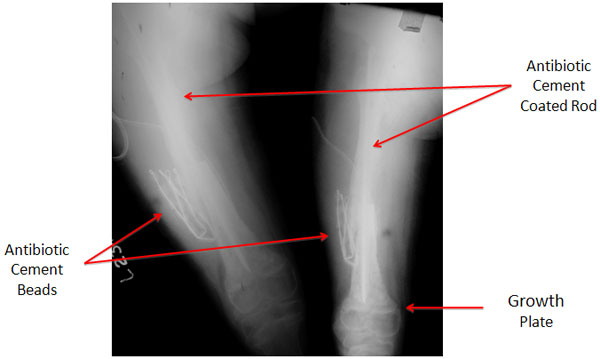

| Post Operative X-rays |

| The post-op x-rays showing the position of the antibiotic cement rod & beads. The fracture has been reduced after removal of the dead bone and tissue. The nail end in the lower portion of femur is just proximal to the growth plate. |